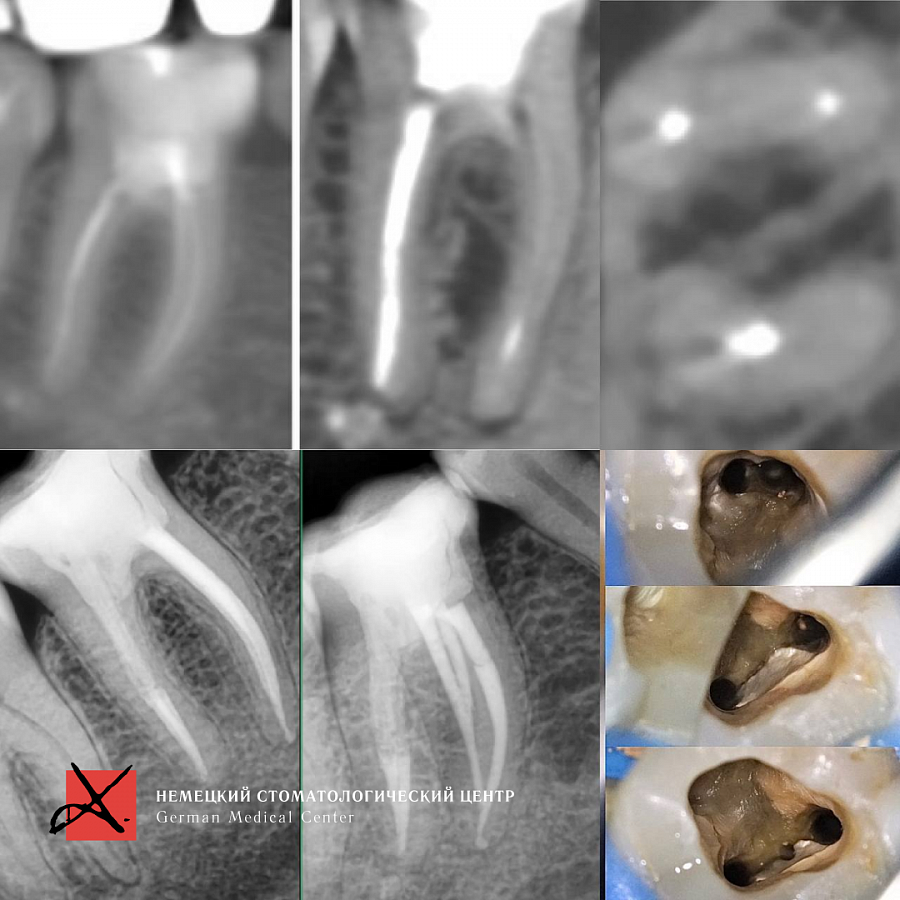

Этапы лечения

Лечение каналов под микроскопом

Результат лечения